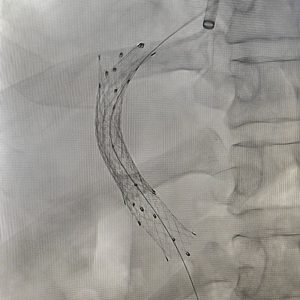

1. TIPS Procedure & TIPS Reduction

The Problem: Severe liver cirrhosis can cause critically high blood pressure in the portal vein (portal hypertension), leading to life-threatening complications like variceal bleeding or stubborn fluid buildup in the abdomen (ascites) that doesn’t respond to medication.

Our Solution: The TIPS (Transjugular Intrahepatic Portosystemic Shunt) procedure creates a new channel within the liver to divert blood flow and reduce this dangerous pressure. If the shunt becomes too wide and causes complications, a TIPS Reduction procedure can be performed to adjust its size and restore balance.

Patient Benefit: A life-saving intervention for uncontrolled bleeding and a highly effective treatment for debilitating ascites.